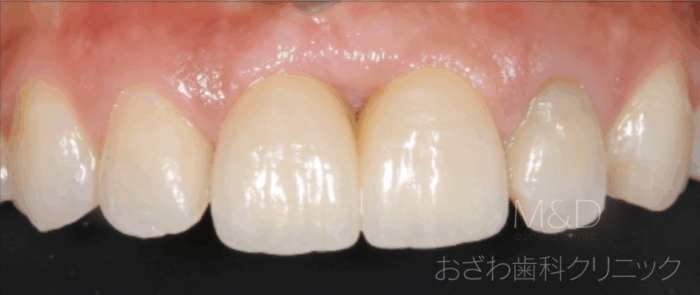

術後

前歯2本を失っていてしまいましたが、入れ歯ではなくご自身の歯のように美しい見た目の審美インプラント治療も行ております。